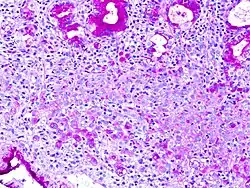

В гистологии перстневидными клетками называют клетки с большой вакуолью. Перстневидные клетки являются злокачественными и, как правило, обнаруживаются в карциномах. Перстневидные клетки наиболее часто выявляются при раке желудка, однако могут возникать в любом типе тканей, включая простату, мочевой пузырь, жёлчный пузырь, молочные железы, толстый кишечник, строму яичников и тестикулы.